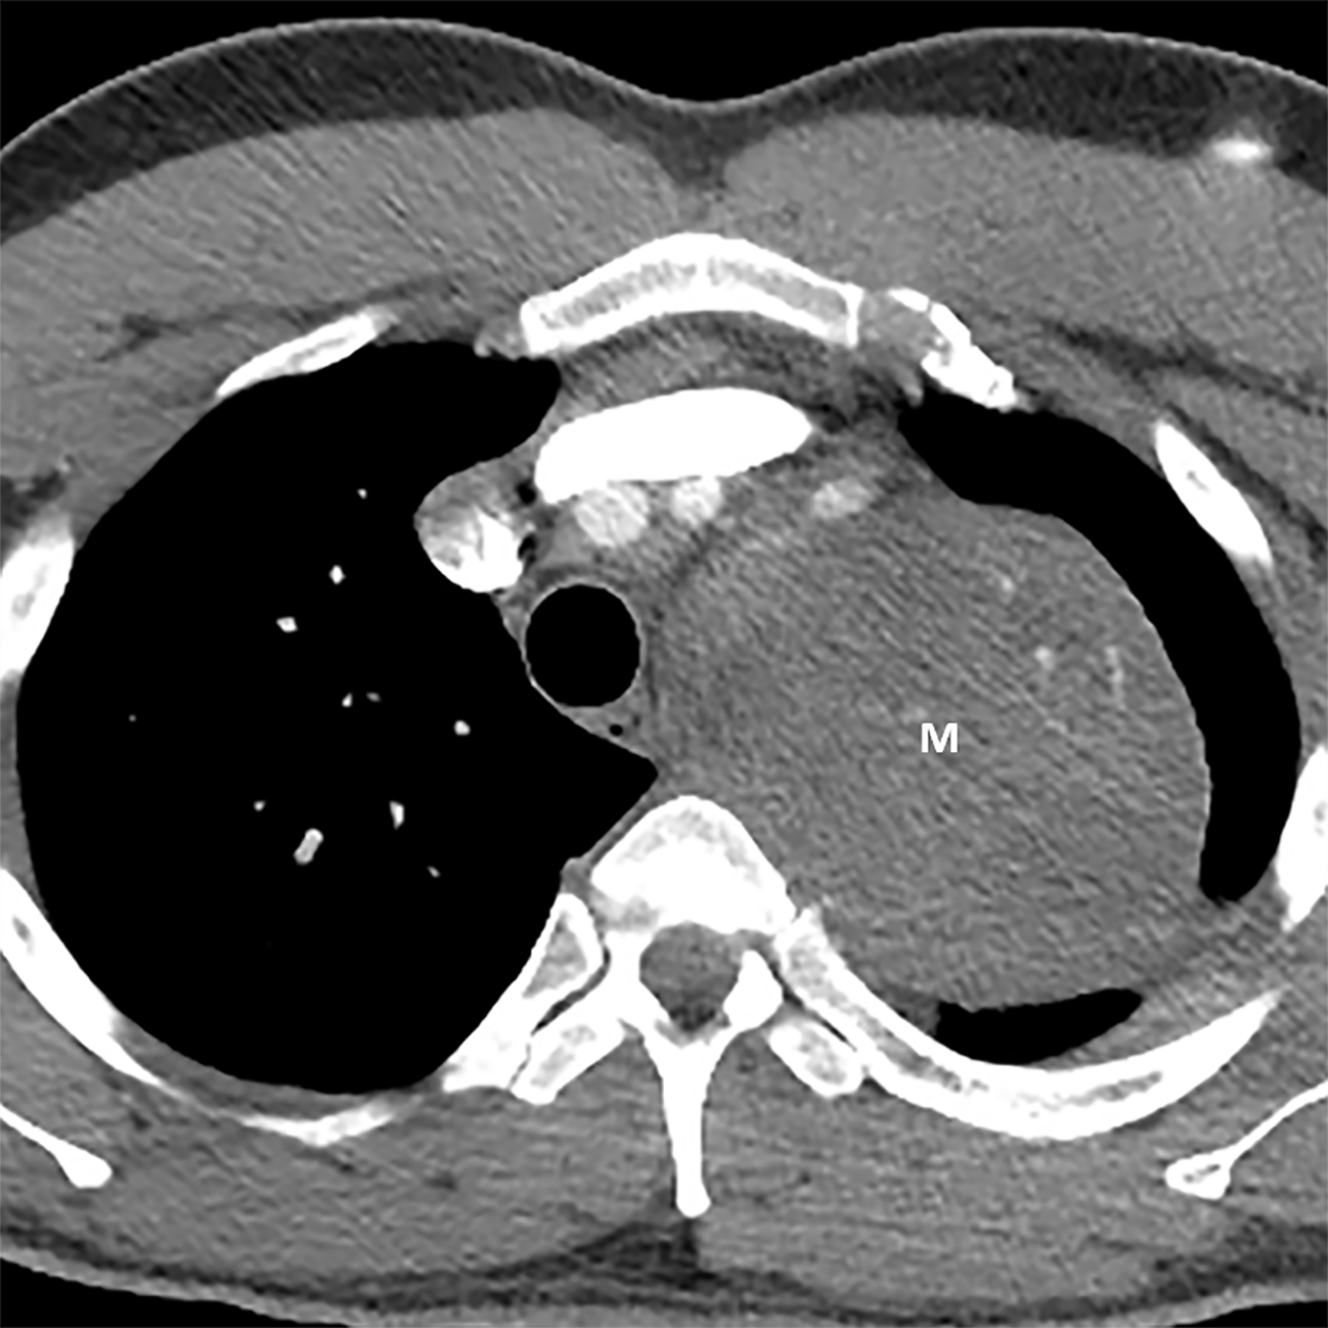

From www.sciencephoto.com

Thymus cancer, crosssection chest CT scan Stock Image C038/9061 Thymic Malignancy Oncology The most relevant differential diagnoses include lymphomas (hodgkin's or non. Thymomas and thymic carcinomas are rare tumors that form in cells on the thymus. Patients are treated with chemotherapy, radiation therapy. Thymomas grow slowly and rarely spread. Thymic carcinoma, or type c thymoma, usually is diagnosed at an advanced stage. Thymic epithelial tumours are the most frequent cause of anterior. Thymic Malignancy Oncology.

From www.alamy.com

THYMUS CANCER, CT SCAN Stock Photo Alamy Thymic Malignancy Oncology Thymic carcinoma, or type c thymoma, usually is diagnosed at an advanced stage. Thymic epithelial tumours are the most frequent cause of anterior mediastinal mass, accounting for 35% of cases; Thymoma and thymic carcinoma treatment options include surgery, radiation therapy, chemotherapy, chemoradiation, and. Thymoma and thymic carcinoma treatment options include surgery, radiation therapy, chemotherapy, chemoradiation, and. Thymomas and thymic carcinomas. Thymic Malignancy Oncology.